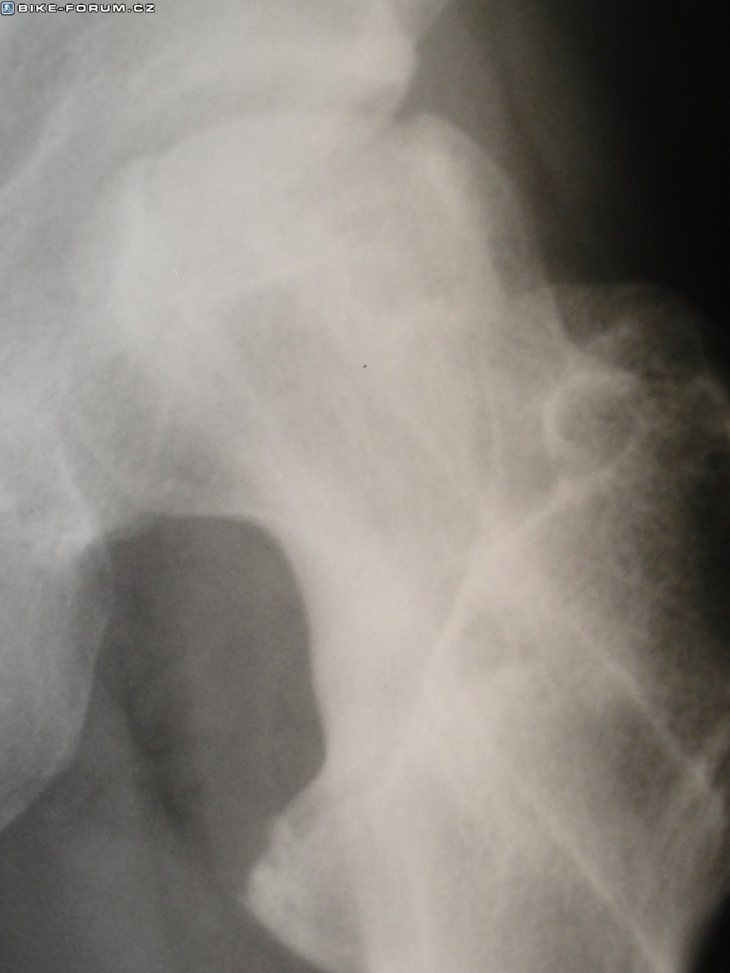

Poúrazová nekróza hlavice

14dnů starý RTG…jde to do háje :(

orca1:dik.AVN=a­vaskulární nekróza(odumírání kosti nedostatkem výživy)

K Landisovi:má HIP resourfacing(což je jen čepička),toto u mě nelze.Musím mít kvůli velké AVN klasický TEP :(